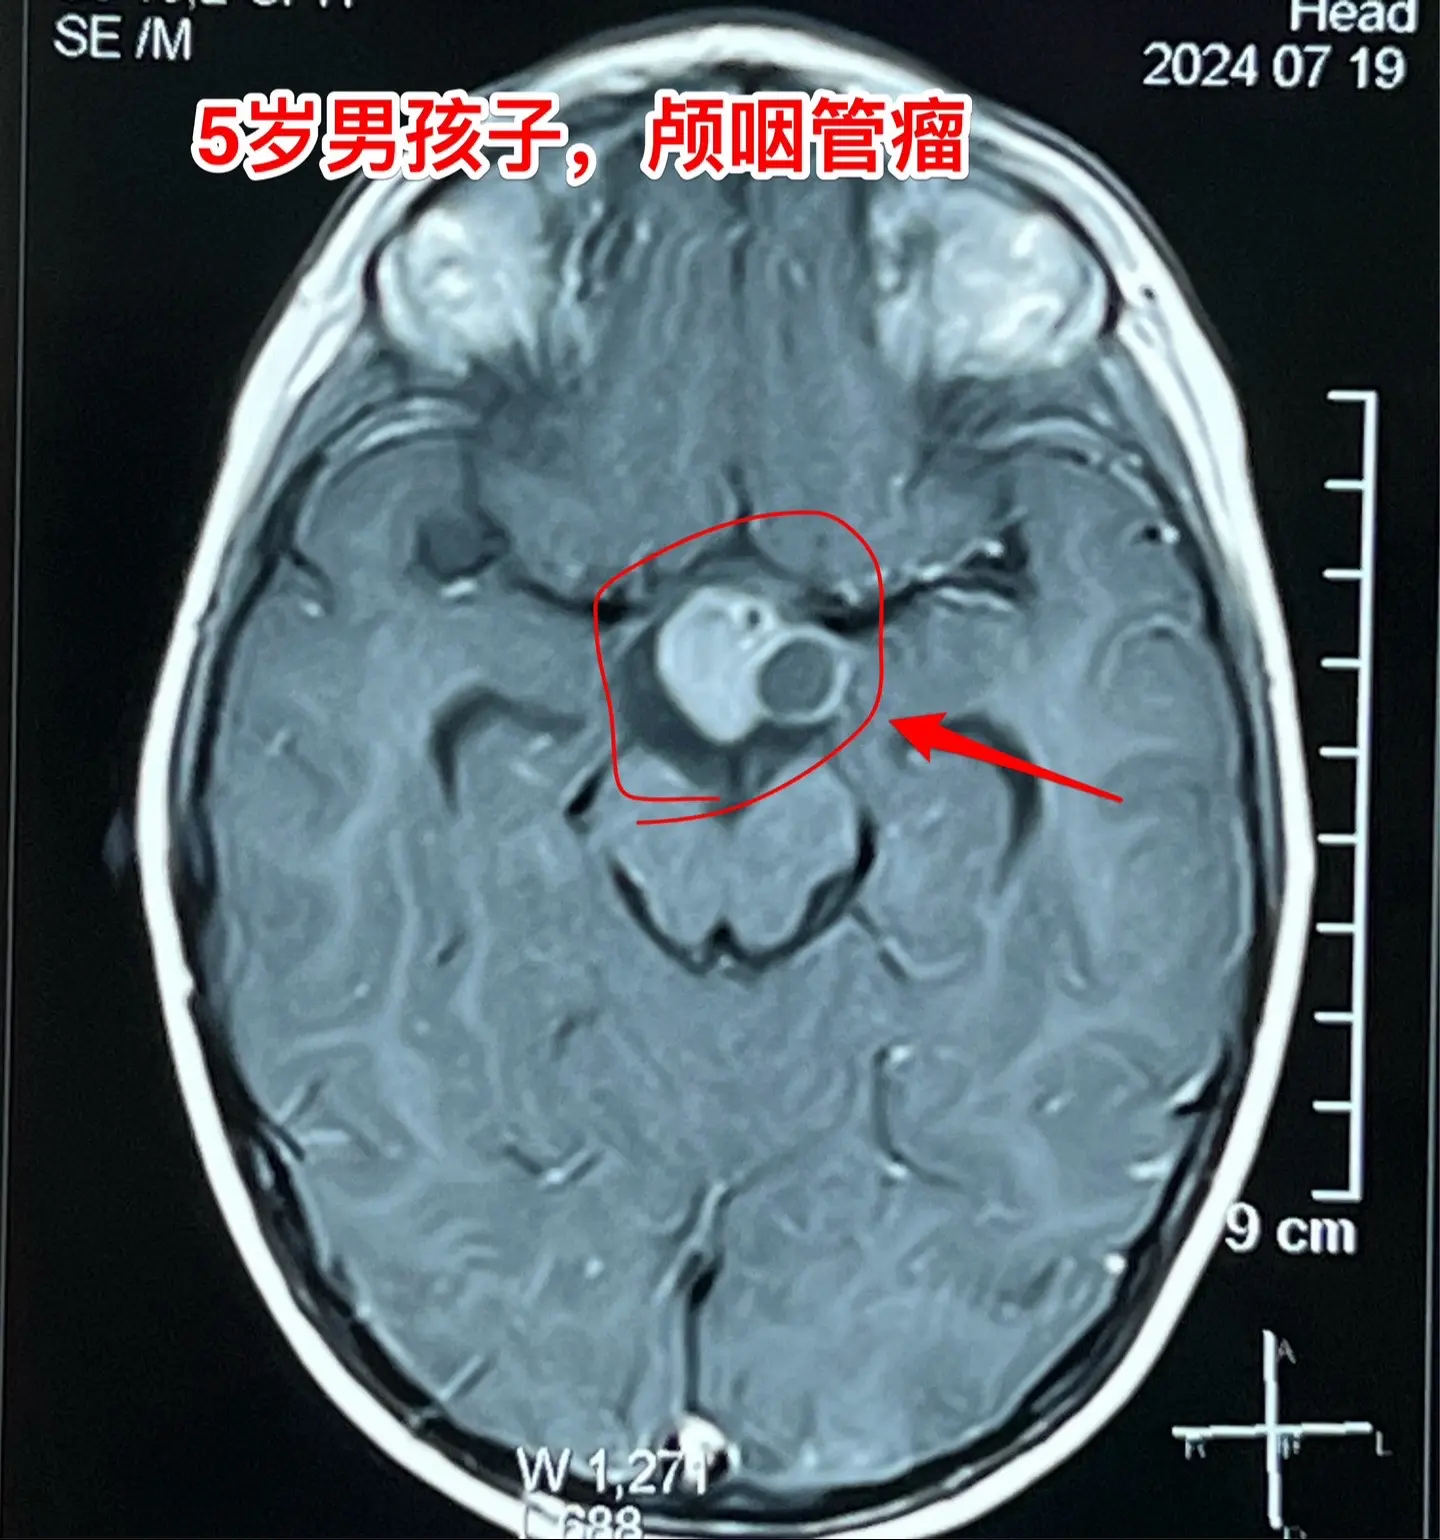

一天两台颅咽管瘤手术对于我们科是常态!7月24日我们科按常规安排了两台颅咽管瘤:第一个5岁男孩子,广东人,因为身高增长缓慢发现了颅咽管瘤。第二个是25岁的三门峡市男性,因为视力下降发现了颅咽管瘤。两个手术都顺利完成。 这样的手术安排对于我们三博脑科医院神经外科八病区来说几乎是常态。有时候一天完成两台复发颅咽管瘤手术,最多的时候一天完成三台颅咽管瘤手术。应该说如果一天只作一个颅咽管瘤手术是比较合理的,一天作两个劳动强度是很高的,不值得提倡。